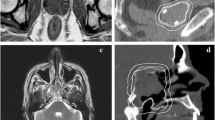

The Fast sequence scan was able to be completed on all patients with no modifications required by the system. This sequence was able to be converted to sCT as per Dowling et al. [11], with no additional artefacts seen in qualitative review of the fast MRI sequence scan or converted F-sCT. An example of the standard MRI and fast MRI, as well as the corresponding S-sCT and F-sCT can be seen in Fig. 1.

The potential trade-offs between reducing MR imaging time and the effects on the MR image quality and subsequent sCT generation accuracy should be considered [32]. A reduction in TR will produce an image with increased contrast between water and fat, being more T1-weighted [25]. An increase in the echo train length, the turbo factor, may increase the potential for artefacts, reducing signal-to-noise and image contrast and causing blurring in the image [33]. Changes in the partial Fourier factor may produce a time reduction in the scan by reducing the amount of k-space data acquired in the phase encoding direction, producing an image with a reduced signal-to-noise ratio [28]. Increasing the imaging acceleration factor will also alter the k-space data acquired, which may produce aliasing artefacts and reduce signal-to-noise [26, 34, 35]. Qualitative comparison of the fast MRI and standard MRI patient images did show a decreased signal-to-noise and some blurring in the fast MRI images, as can be seen in the MRI images in Fig. 1. However, these issues did not significantly affect the generated sCT for this cohort of patients.